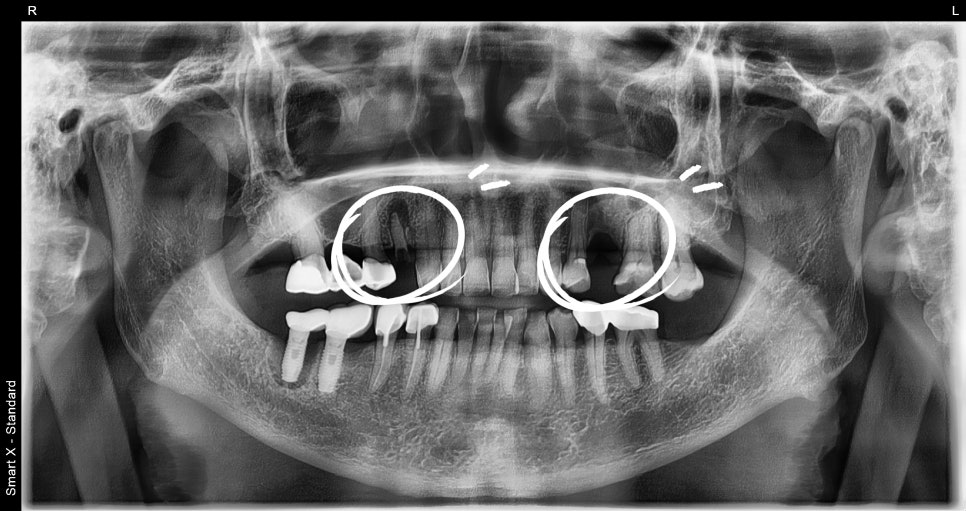

파노라마 X-ray와 구강검사 결과,

치조골 상태가 양호하여 보험 임플란트 식립이 가능한 상태였습니다.

② 보험 임플란트 2개 식립

– 국소 마취 하에 하악 어금니 부위에 임플란트 2개를 식립했습니다.